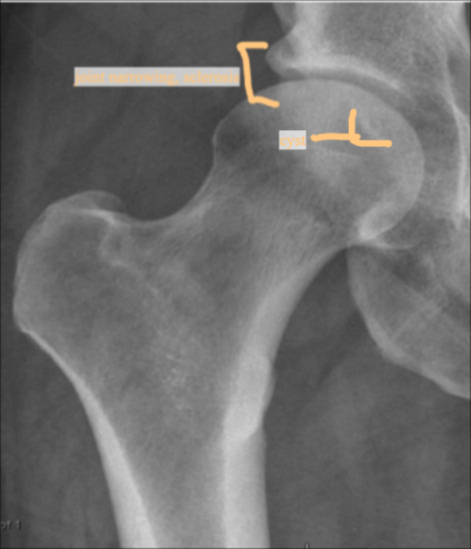

AP HIP Joint line narrowing, osteophyte formation, subchondral sclerosis and cysts, no obvious deformity